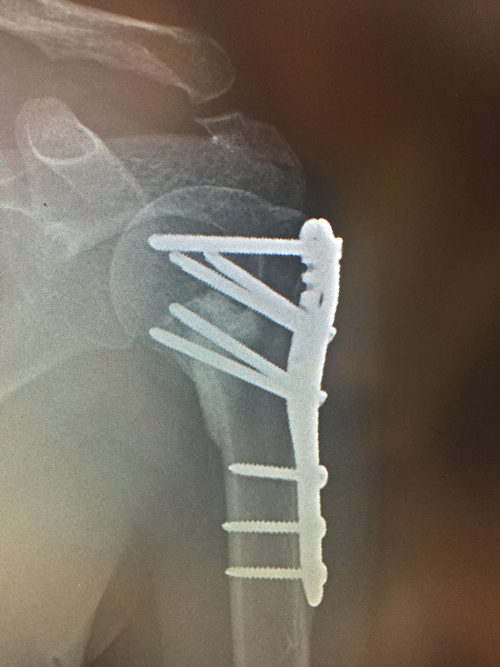

Surgery allows the fracture fragments to be re-aligned. The fracture is then held in a reduced position using a locking plate. Surgery is done thro the deltopectoral interval under general anaesthesia. Following surgery the arm is in a sling for 6 weeks although gentle passive movement is allowed.

All patients develop a stiff shoulder following surgery. Individuals under 30 or over 60 often get moving quicker. It appears that the inflammatory response to the injury and surgery is not as pronounced. It is inflammation in the shoulder which causes stiffness (known as a frozen shoulder). While 95% of surgery is uneventful complications may occur.

In some instances if the fracture is very displaced in the presence of osteoporotic bone it is better off being replaced with a reverse geometry total shoulder.